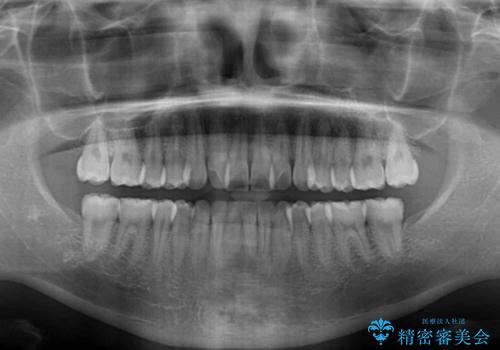

前歯のクロスバイト インビザラインによる矯正治療

- 上下のクロスバイトと前歯のデコボコを気にして来院された患者様です。

インビザラインを用い、IPR(歯と歯の間を削る)と歯列全体を拡大させることで、歯並びを整えていくこととしました。

治療を急いでいらっしゃらなかったため、のんびりと治療を進めていきました。3年以上の期間を要しましたが、きれいな口元に仕上がりました。